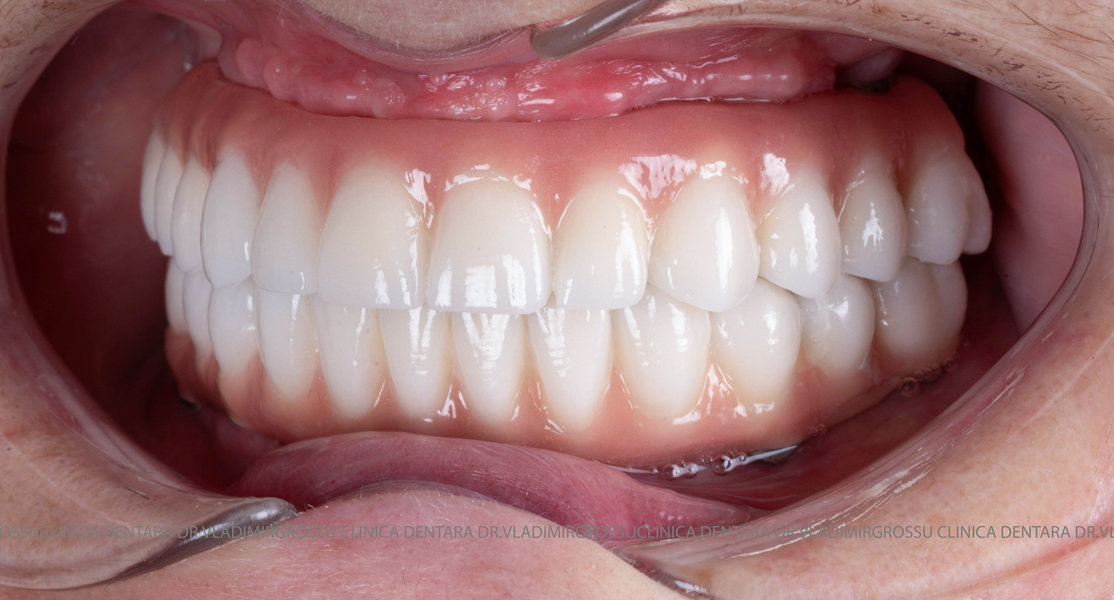

- Posibilitatea realizării unei proteze cu 12-14 dinți, oferind un aspect estetic natural și funcționalitate optimă.

Pentru pacienții cu edentație extinsă sau dinți nefuncționali, metoda All-on-6 oferă o alternativă modernă și eficientă la proteza mobilă, asigurând o restaurare fixă, stabilă și estetică a danturii. Datorită distribuirii optime a implanturilor și a tehnologiei avansate implicate, această soluție îmbunătățește considerabil calitatea vieții, confortul și funcționalitatea orală. Succesul tratamentului depinde de o planificare riguroasă, de utilizarea componentelor de calitate și de competența echipei medicale, ceea ce face ca alegerea unei clinici specializate să fie esențială pentru obținerea unor rezultate durabile și sigure.